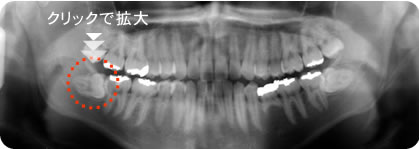

今日行ったところでは、普段どおりに歯の検診、レントゲン撮影(上記の画像は私のではありません)、そして、診断の内容を医師から説明を受ける。